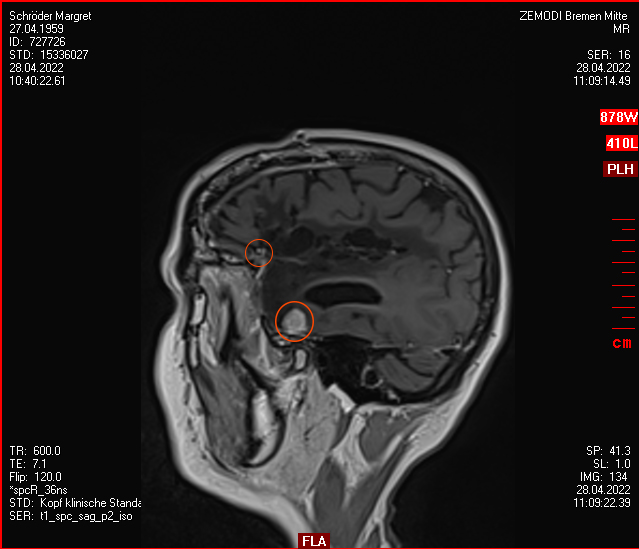

Januar 2021: Ein Kampf gegen Erbsen im Kopf mit modernen Mitteln

Also habe ich mich entschieden, dem Rezidiv nicht mehr länger beim Wachsen zuzusehen und habe Kontakt aufgenommen zur Strahlenmedizin in Hamburg, iCERA – Spezialisten für Radiochirurgie – „Präzisionsstrahlenbehandlung - geschnitten wird dabei nicht“. Das ging alles ziemlich schnell, im Dezember die Bilder auf CD nach Hamburg geschickt, ein Telefongespräch mit dem Professor, der zu einer Vorstellung bei ihm geraten hat, ein Vorgespräch im Januar und nun ist es am 26.01.2021 schon passiert – das Gammknife hat aus fast 200 Strahlenquellen für ca. 20 Minuten aus verschiedenen Richtungen auf den Tumor „geschossen“, so dass am Tumorpunkt die Strahlen zusammenfanden und so gemeinsam in diesen paar mm³ genug Energie entstand, um einen Schaden an den Zellen anzurichten ohne das gesamte Gehirn zu schädigen. Große Medizintechnik der Neuzeit. Meine Krankenkasse zahlt, was erstaunlicher Weise nicht für alle Kassen gilt.

Nun muss man warten, dass der Körper auf richtige Weise auf die Behandlung reagiert und das Wachstum des Tumors gestoppt worden ist. Das wird man erst Ende April sehen, wenn ich zum nächsten MRT nach Hamburg fahren werde. Aber weiter gilt, mir geht es gut, nix tut weh und all meine kleinen Tests zur Funktion des Gehirns (schweres Sudoku, Einkaufen mit dem Rad und bei schlechtem Wetter (Nieselregen/Schnee auf der Brille) und diese Webseite fix erweitert) haben geklappt, mehr will ich nicht!